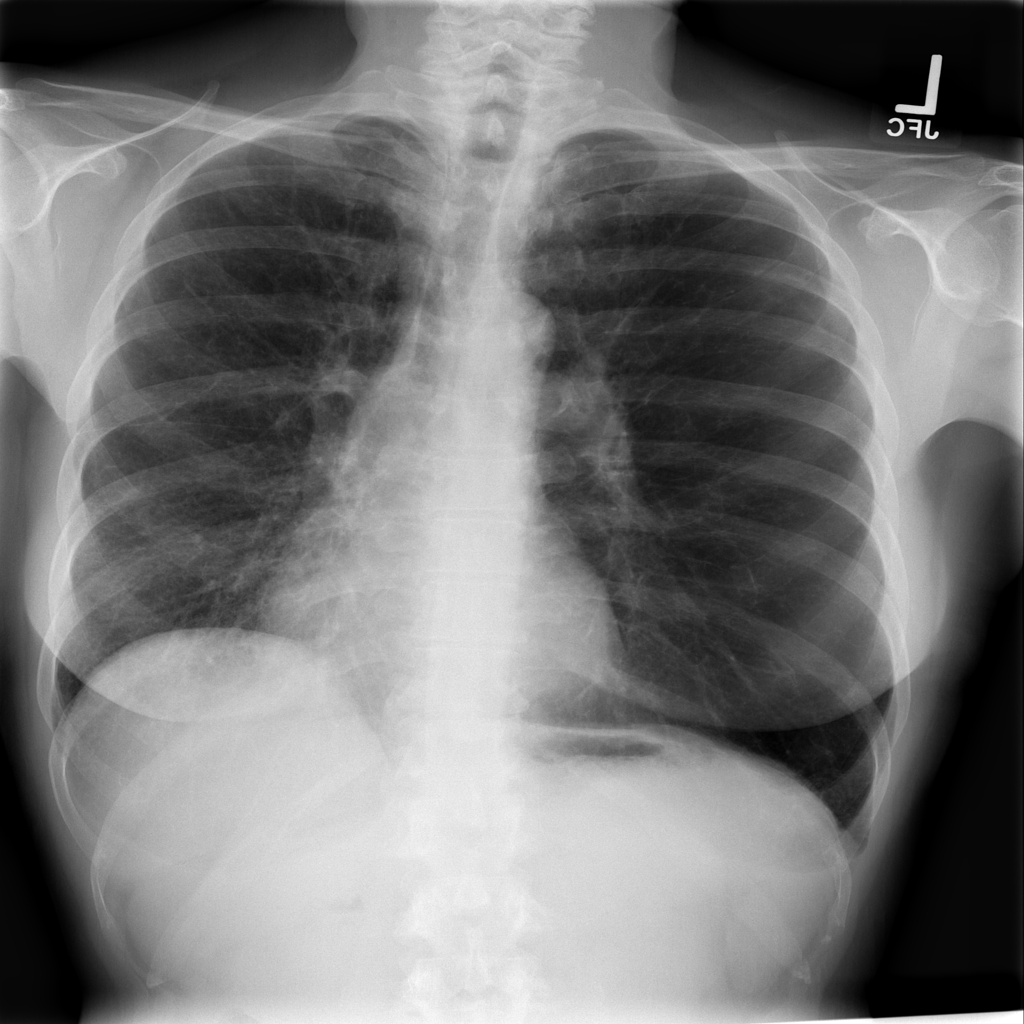

PAT-55FC · IMG-032Emphysema

PAT-55FC · IMG-032

AP